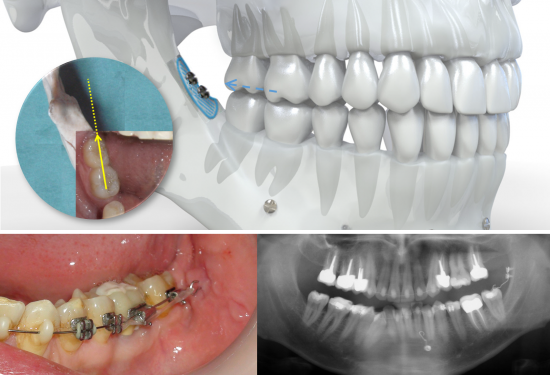

Système CT8 - Mésialisation molaire inférieure

La mésialisation molaire peut être exécutée grâce au Kit Mésialisation molaire mandibulaire pour une action unilatérale avec le CT8-1. Elle peut également être exécutée grâce au Kit Mésialisation molaire mandibulaire bilatérale pour une traction exercée des deux côtés par le CT8 tunnel.